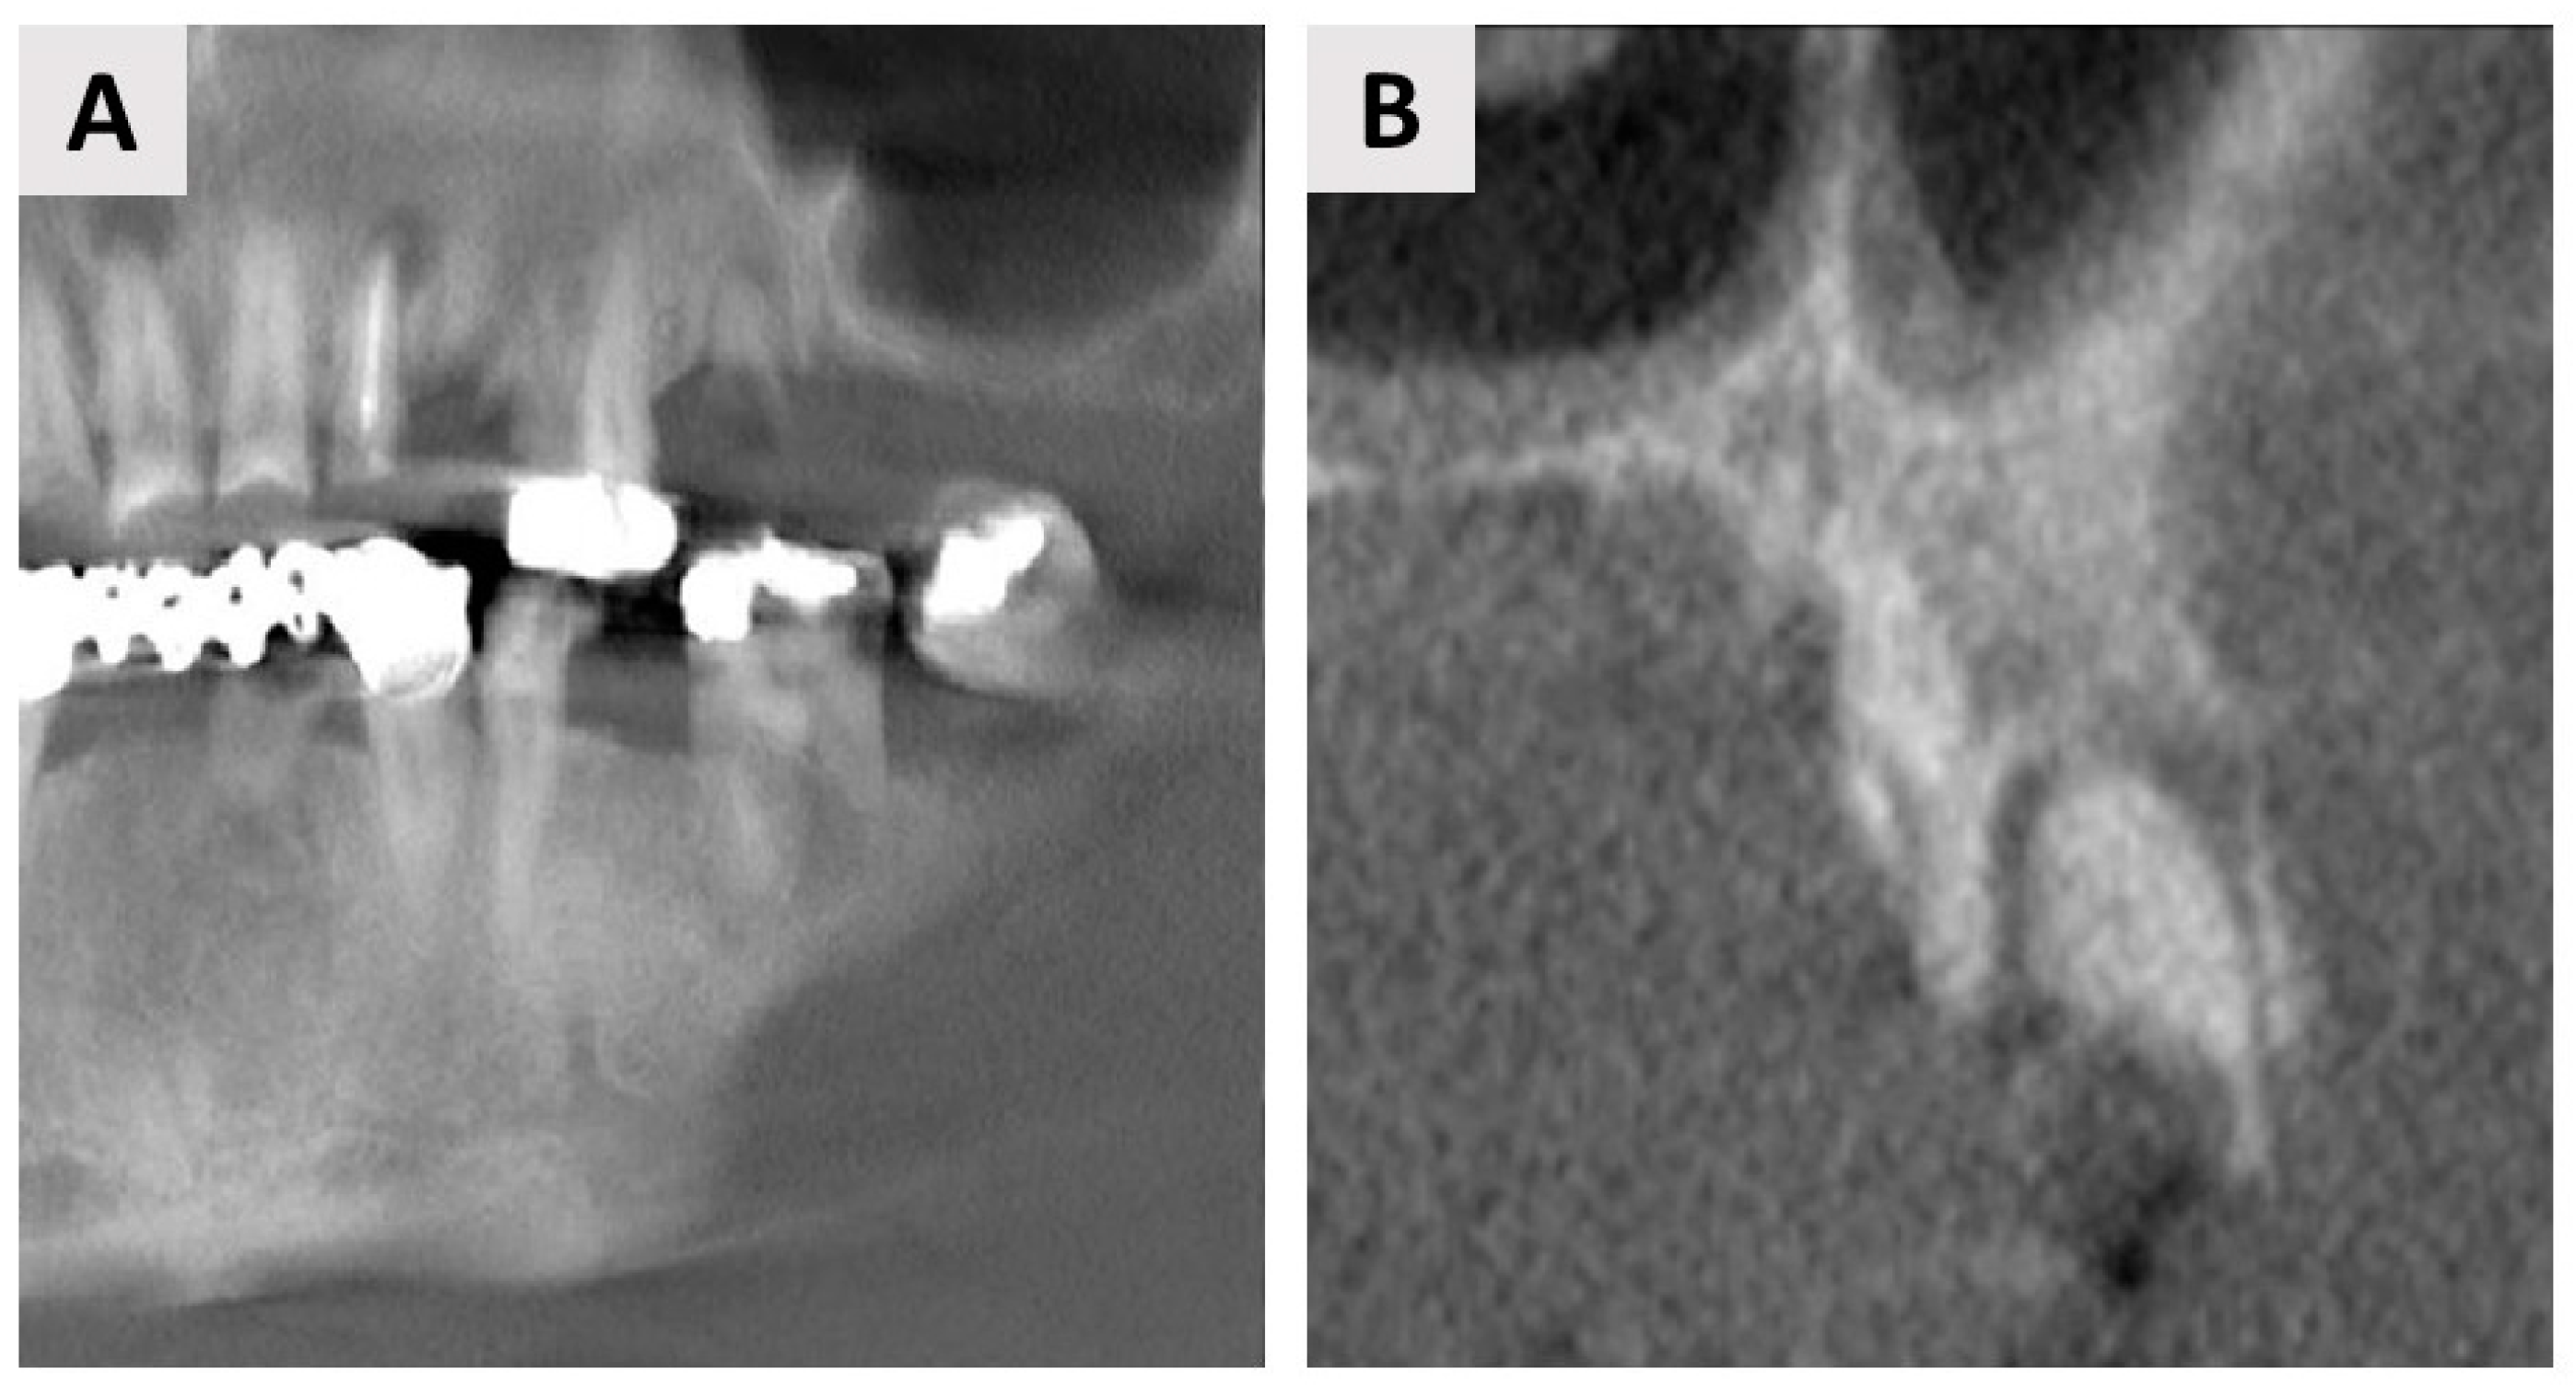

3. Case Report One: GBR with Delayed Implant Placement